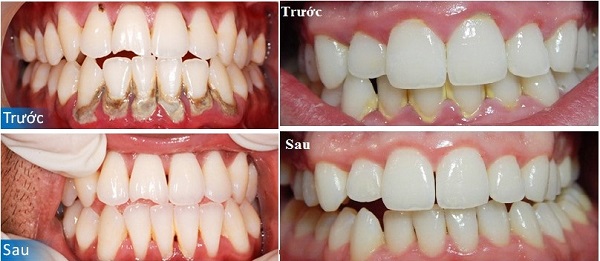

V. Một số ca điều trị viêm nha chu tại Dentel: